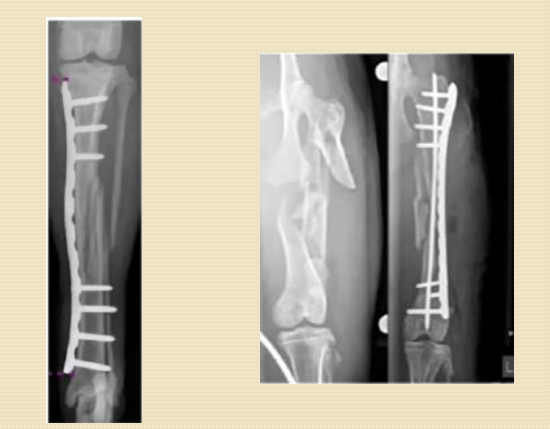

PLACAS Y TORNILLOS

TIPOS DE PLACAS

- Placas de compresión dinámica (DCP)

- Placas LC-DCP (contacto limitado)

- Placas bloqueadas

FUNCIONES DE LAS PLACAS ÓSEAS

- Compresión interfragmentaria

- Neutralización

- Sostén (refuerzo o puente)

INDICACIONES GENERALES PARA CIRUGÍA CON PLACAS

- Fracturas con fragmentos reconstruibles.

- Fracturas que requieren reconstrucción anatómica y escasa formación de callo.

- Fracturas que requieren compresión.

- Artrodesis.

- Placa puente en fracturas no reconstruibles.

INDICACIONES PARA PLACAS DE NEUTRALIZACIÓN

- Osteotomías o fracturas reconstruibles con tornillos de tracción o cerclajes.

- Colocada en el lado en tensión para neutralizar torsión, doblamiento, compresión o distracción.

INDICACIONES PARA PLACAS DE COMPRESIÓN

- Fracturas transversas u oblicuas cortas.

- Osteotomías y artrodesis.

- La placa queda en tensión y los fragmentos en compresión.

- Colocación en el lado bajo mayor tensión:

- Lateral del fémur

- Medial o craneal de la tibia

- Craneal o lateral del húmero

- Craneomedial o craneal del radio

INDICACIONES PARA PLACAS BLOQUEADAS

- Tornillo bloqueado no comprime el periostio → conserva vascularización.

- Útil en fracturas conminutas y huesos osteoporóticos.

- Agujero combinado permite compresión + bloqueo.